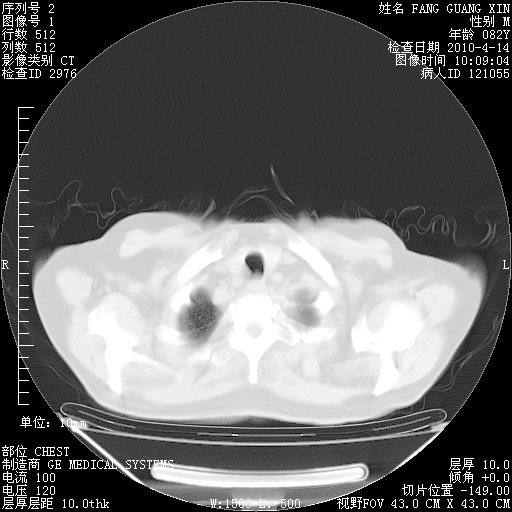

4月14日肺部CT